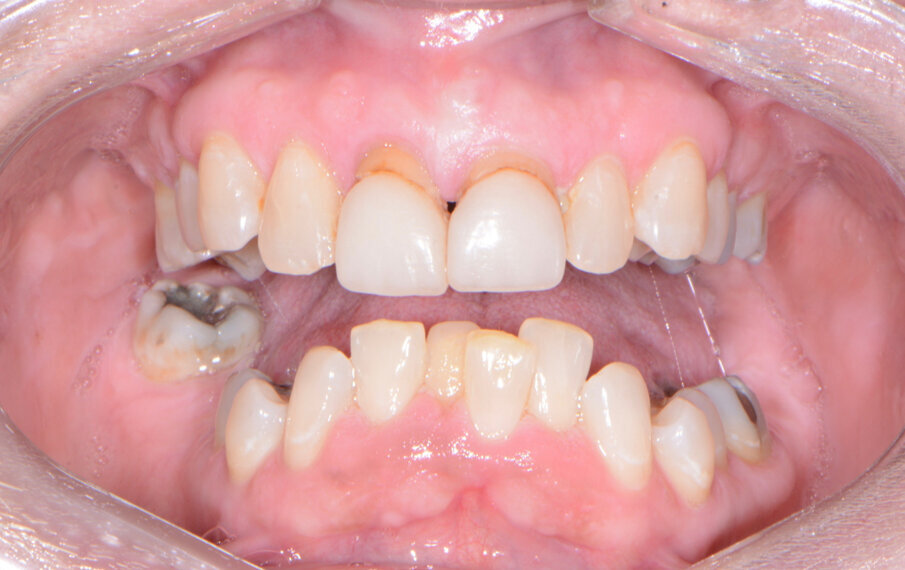

A patient presented to my practice for a consultation wanting to restore her dentition to proper form and function (Fig. 1). She complained of generalised discomfort and mobility in these teeth, apparently due to advanced periodontal disease. There were several teeth in both arches that had Grade III mobility upon clinical examination. Also, there was hyper-eruption in the anterior mandibular dentition due to her jaw position with a deep impinging bite (Fig. 2).

The clinical evaluation included information regarding lip length and support, the position of the natural teeth, occlusion, restorative space and phonetics. In addition, digital images of frontal, side and occlusal views of the dentition as well as facial shots were captured with a Nikon D7200 (PhotoMed).

To further develop the treatment plan, diagnostic model impressions were taken using Silginat polyvinylsiloxane impression material (Kettenbach), poured up and forwarded to the dental laboratory. These models were then mounted on an articulator (Stratos 100, Ivoclar) for further analysis in order to meet the patient’s aesthetic and functional needs.